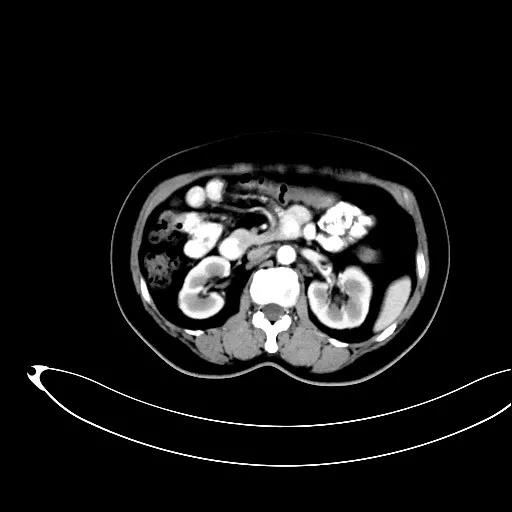

排除禁忌后,在全麻下行“次广泛子宫切除+双附件切除+大网膜切除+阑尾切除术+盆腔淋巴结及腹主动脉旁淋巴结切除术”。术中切除腹主动脉左旁、右旁及后方淋巴结,达左右肾动静脉水平。多个淋巴结呈融合状态,长径约3-5cm。手术由陈亮副主任医师和宋趣清主治医师完成。

妇科一病区严格遵循指南推荐,在影像学或探查淋巴结阳性的晚期卵巢癌中,若能达到满意减瘤,仍常规行盆腔及腹主动脉旁肿大淋巴结切除/清扫术(如下图举例)。通过前期初步统计分析,肠系膜下动脉至肾静脉下淋巴结转移阳性率为25%左右,在全部腹主动脉旁淋巴结转移患者中约占30%,显示了肾静脉下腹主动脉旁淋巴结清扫的价值。其对生存的影响有待进一步观察。